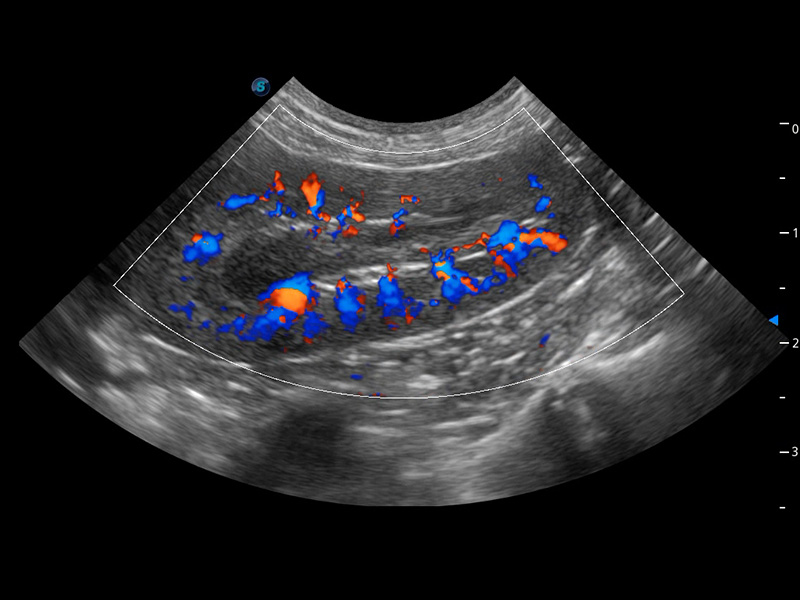

ProPet 60 作为一款高端台式动物超声设备,为动物医生的日常诊断提供了一系列贴合动物临床需求、解决临床实际问题的高级成像功能。凭借全系列高清探头,满足医生对腹部、心脏、生殖、浅表、肌骨等成像的所有需求,切实帮助您提升检查效率,提高诊断信心。

动物是人类最亲密的朋友和最值得信赖的伙伴。百老汇电子游戏官网也一直致力于探索动物专用的超声影像解决方案。 全新推出的ProPet系列,是百老汇电子游戏官网在动物超声影像智能化、专业化、精准化的一次跨越式革新。动物不能用言语来表述自己的不适,通过超声影像,ProPet系列搭建了动物医生与不同物种沟通的“桥梁”,为动物医生注入了“治愈之力”。